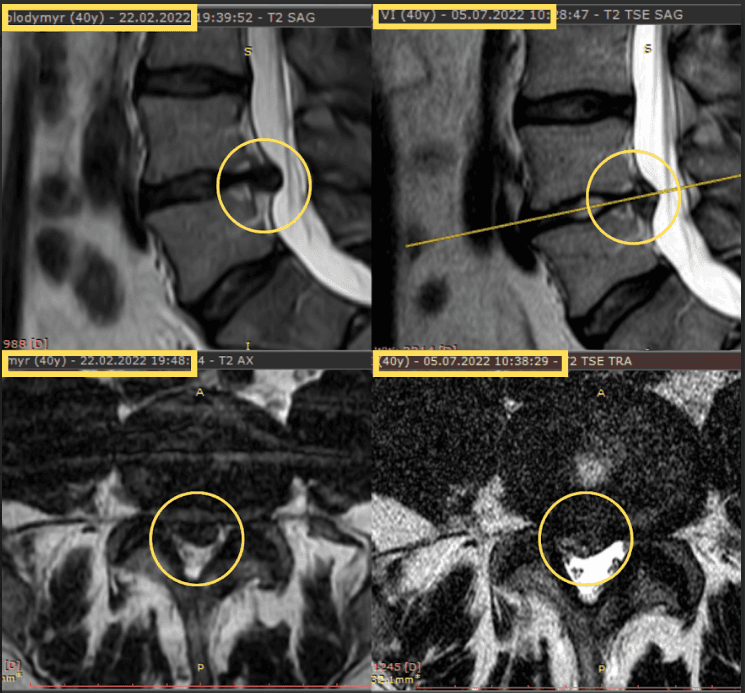

Метод лікування грижі шляхом стимуляції резорбції в Україні був впроваджений у 2020-2021 роках.  Алгоритм оцінки грижі на предмет резорбції, що використовується у клініках – є авторським, розроблений лікарем Боханом А.Ю.